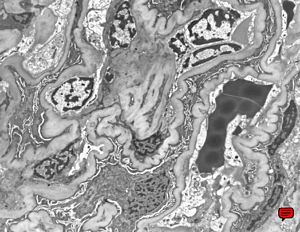

M,53y. | type III membranoproliferative glomerulonephritis